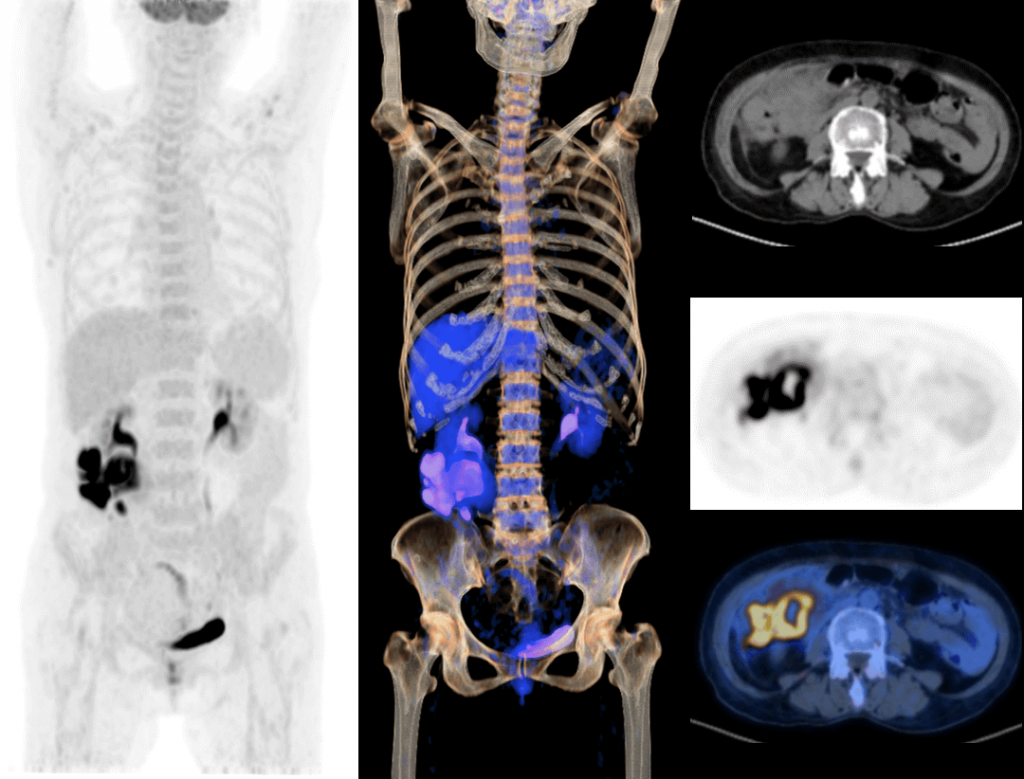

With the unique Integrated-Light-Guide Digital PET technology and a 160-slice CT system, uMI Vista combines high quality functional images with fine anatomical structure visualization. The state-of-the-art reconstruction technology and comprehensive applications further boost diagnostic precision in oncology, neurology and cardiology.

2.9mm NEMA Resolution

Outstanding resolution performance is achieved through systematic imaging chain engineering.

HYPER Iterative Reconstruction

Improves signal-to-noise ratio and contrast recovery to aid lesion detectability and quantitative accuracy.